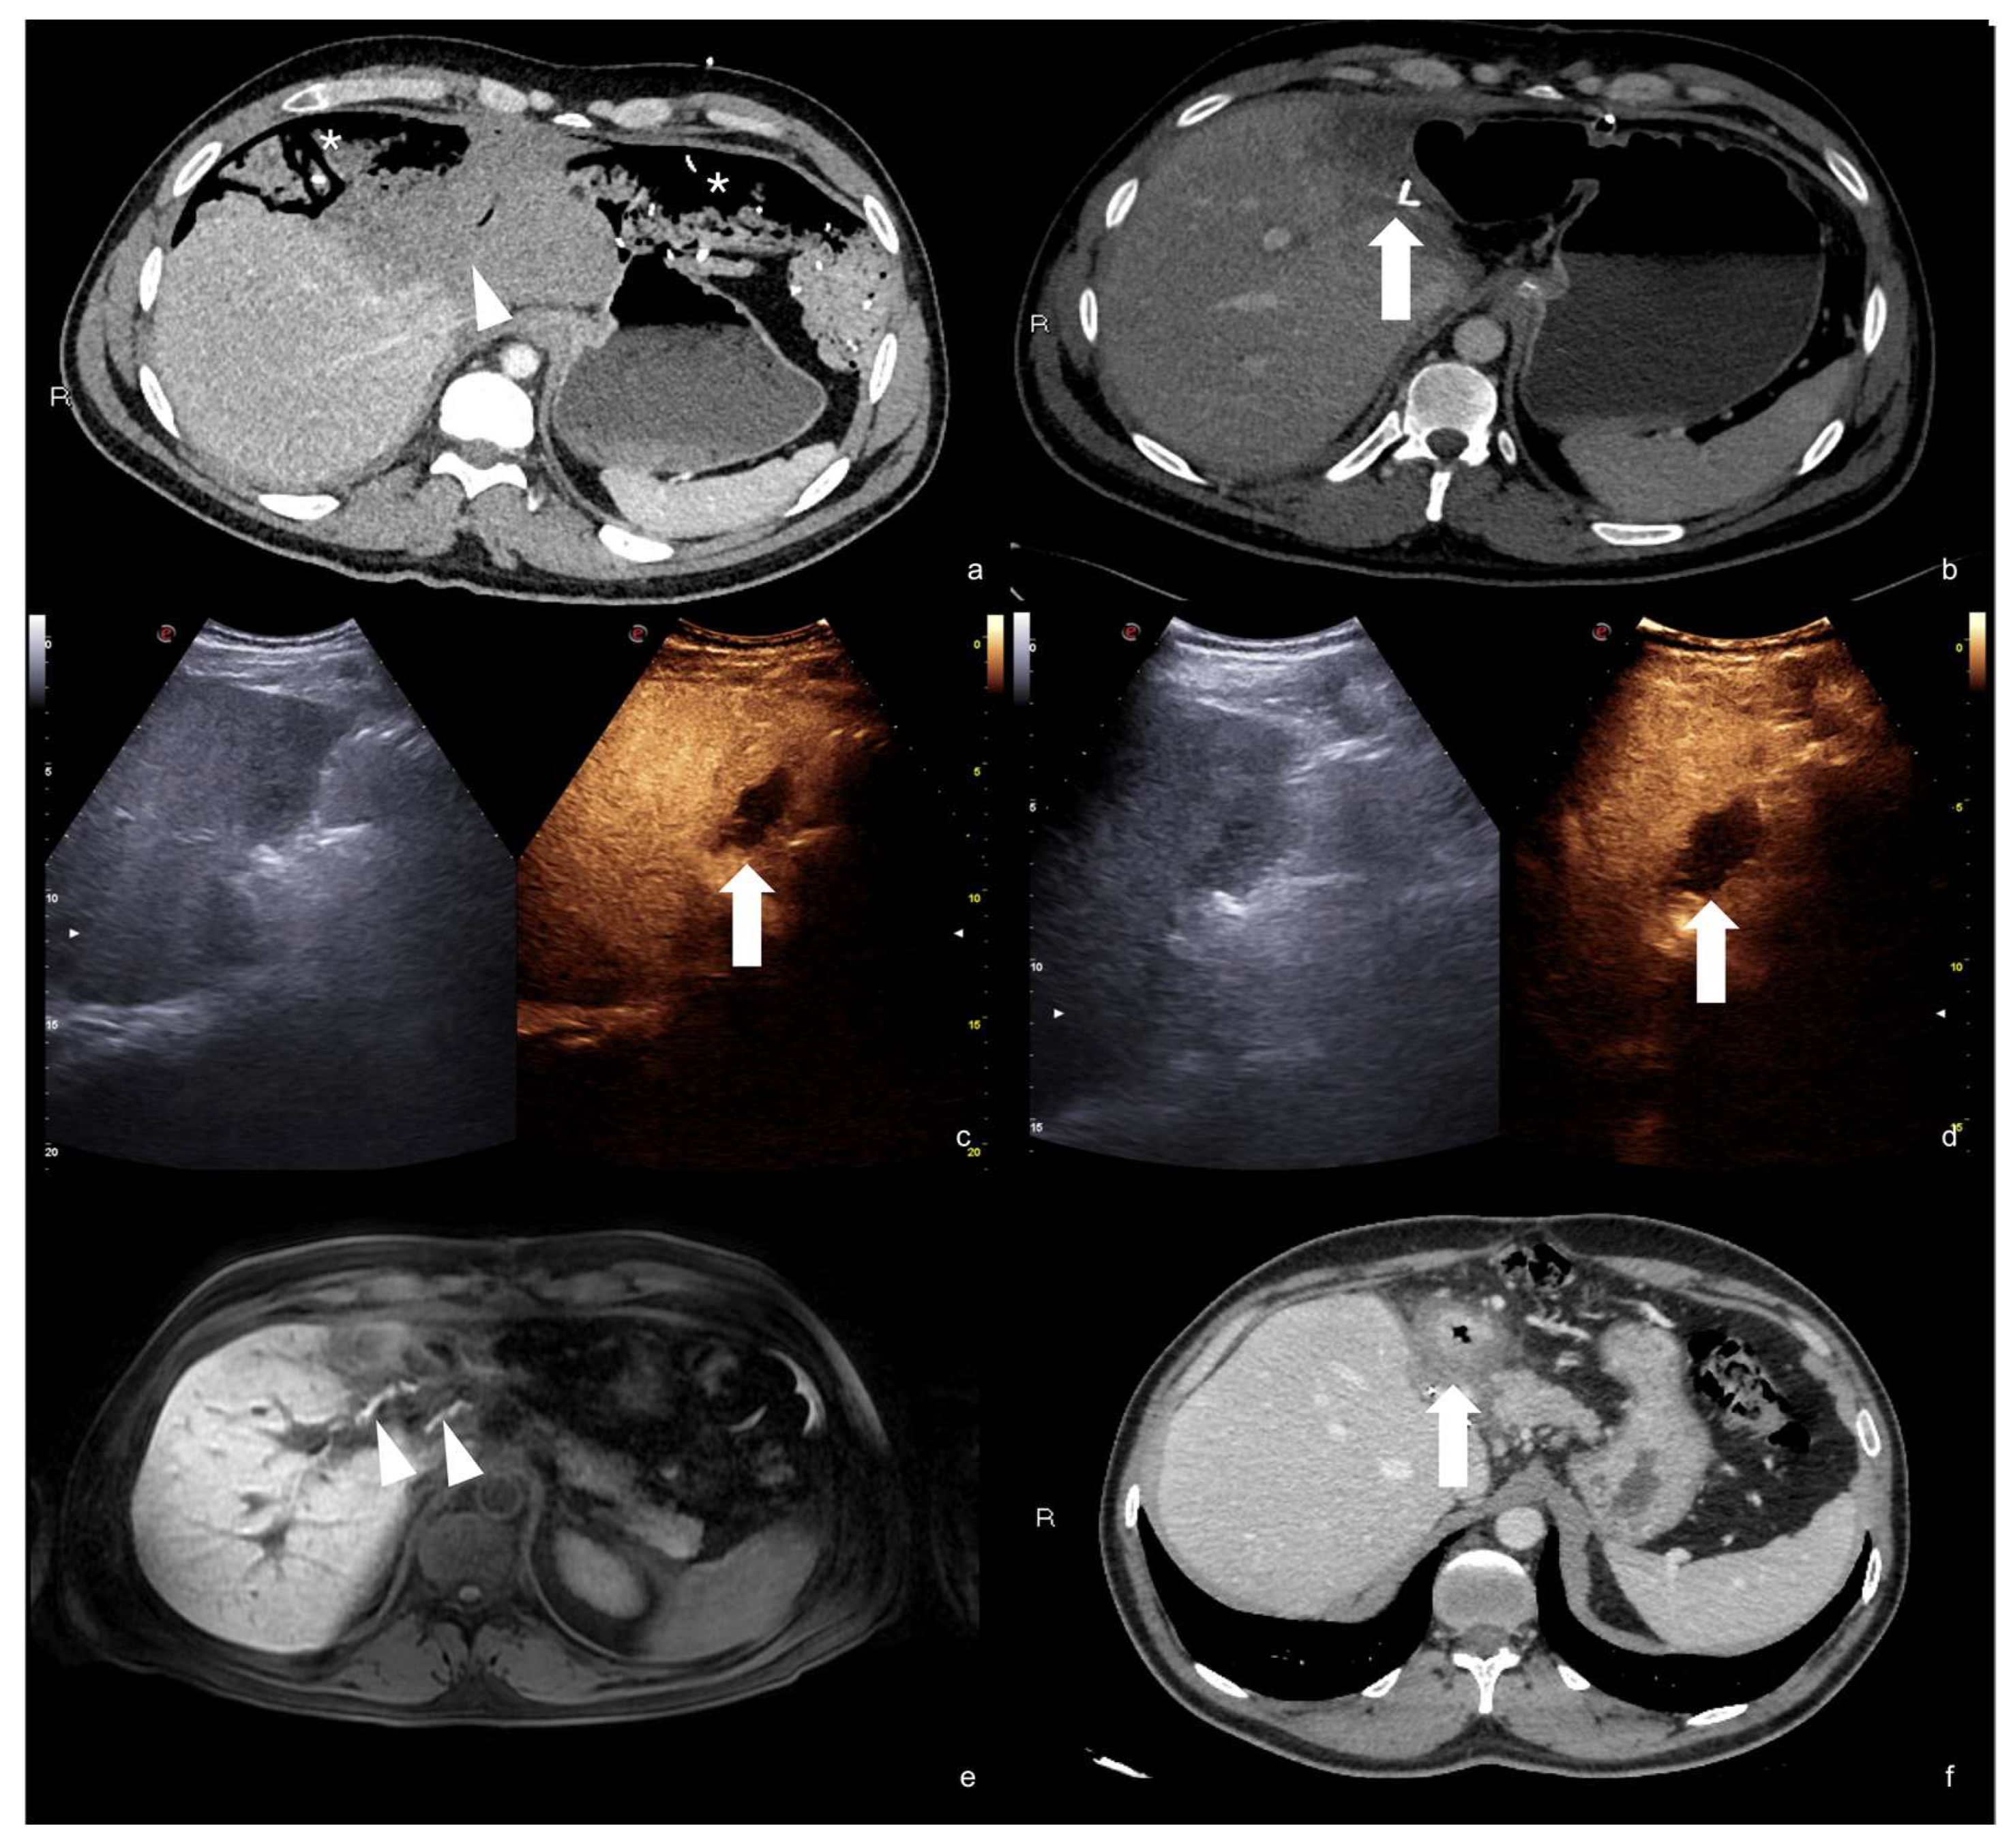

Figure 19.

High grade traumatic splenic injury with vascular complication. Arterial (a) and venous (b) phase CEUS examination in a 25−year-old patient admitted at the emergency department for blunt abdominal trauma, showing multiple splenic lacerations and a voluminous arteriovenous fistula (white arrowhead). Subsequent arterial (c) and portal vein (d) phase contrast-enhanced CT scan further confirmed the diagnosis (black arrowhead).

Figure 20.

CEUS (a) of a 23−year-old man referring to the emergency department for direct blunt trauma to the right flank showed the presence of a small pseudoaneurysm (white arrow) inside the contusion area of the right kidney; the diagnosis was then confirmed at the axial arterial phase contrast-enhanced CT scan (b), as well as at angiography performed for treatment purposes (c).

Arteriovenous fistulas consist of traumatic communication between the arterial and venous systems [1,30]. Fistulas are characterized as asymmetrical, early contrast opacification of a vein during the early arterial phase of the study (Figure 21).

Figure 21.

Companion case of Figure 2b. Renal arteriovenous fistula (white arrowhead) at color–Doppler US (a) and CEUS (b), confirmed (c) at contrast-enhanced CT scan (arterial phase, coronal MIP reconstruction) and subsequent angiography (d).